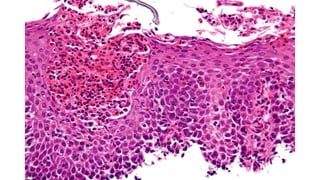

• Hiperplasia extrema da zona basal com

hiperplasia papilar

• Eosinófilos concentrados no epitélio superficial

em oposição à base

• Microabscessos eosinofílicos

• Megranulação eosinófila

• Descamação superficial

• Fibrose da lâmina própria

• Critério Maior

• ≥ 15 eosinófilos por campo de

grande aumento (ampliação de 40x)

no contexto clínico adequado